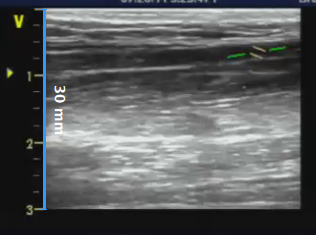

- Locate, in ultrasound image, a range of known distance (30 mm. in the example of figure).

- In the B-mode setup panel, select from the drop-down menu, the distance specified above.

- In the B-mode setup panel, click on the Set B-Mode Calibration button (button remains active).

- Draw a line on the image corresponding to the known distance: click on one end and drag the mouse to the other extreme (press the Shift key or Ctrl+Shift keys on your keyboard if you want the line to be not vertical or horizontal).